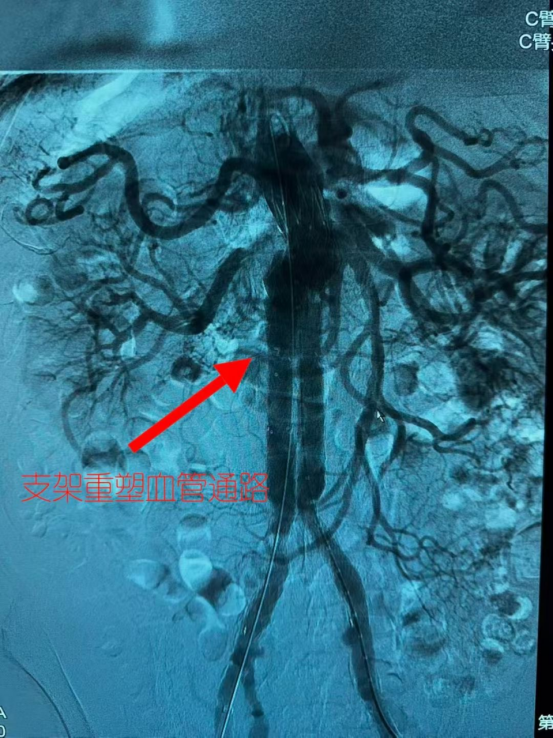

穿刺、导丝进入、造影定位……大屏幕上,那个随着心跳搏动的瘤体,像一只贪婪的怪兽,张着血盆大口。医生们屏息凝神,手中的导丝在错综复杂的血管中艰难穿行。

"支架释放!"

再次造影显示,血流顺利通过,"炸弹"成功拆除!